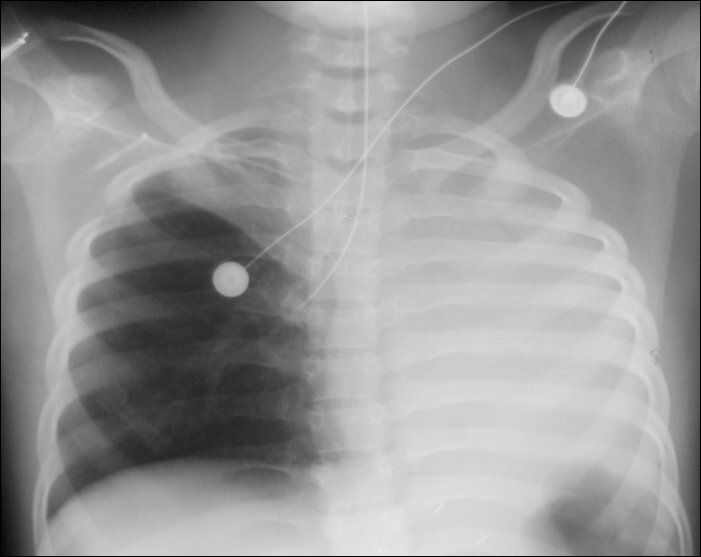

What is the diagnosis? What happened here?

1. Atelectasis RUL due to Endotracheal Tube

2. Atelectasis RUL